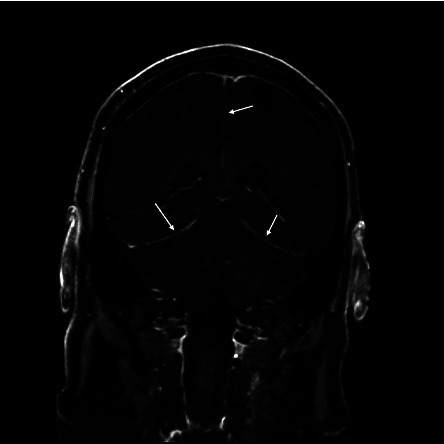

Vancomycin-resistant Enterococcus faecium (VRE) meningitis is rare. It is usually associated with neurosurgical procedures or devices. We describe a case of VRE meningitis from hematogenous spread during persistent bacteremia in an immunocompromised patient who received haploidentical bone marrow transplant for VEXAS syndrome. The bacteremia and meningitis were successfully treated with combination of intravenous (IV) daptomycin, ceftaroline, and linezolid.